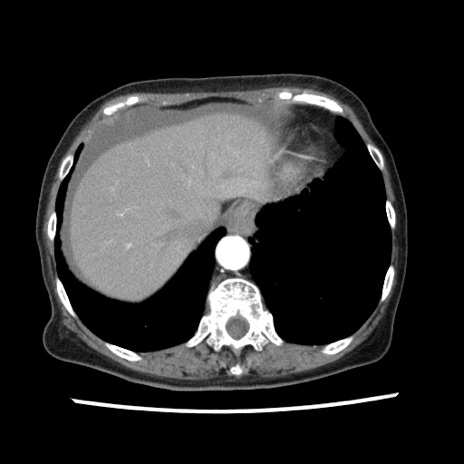

矢状断像

【症例】80歳代女性

【主訴】腹痛

【現病歴】8時間前から腹痛あり来院。

【既往歴】糖尿病、脂質異常症、子宮体癌にて子宮全摘術

【身体所見】意識清明・会話良好だが腹痛で苦悶様、全腹部にわたって反跳痛と圧痛あり

【データ】WBC 13600、CRP 0.14、LDH 224、CK 90